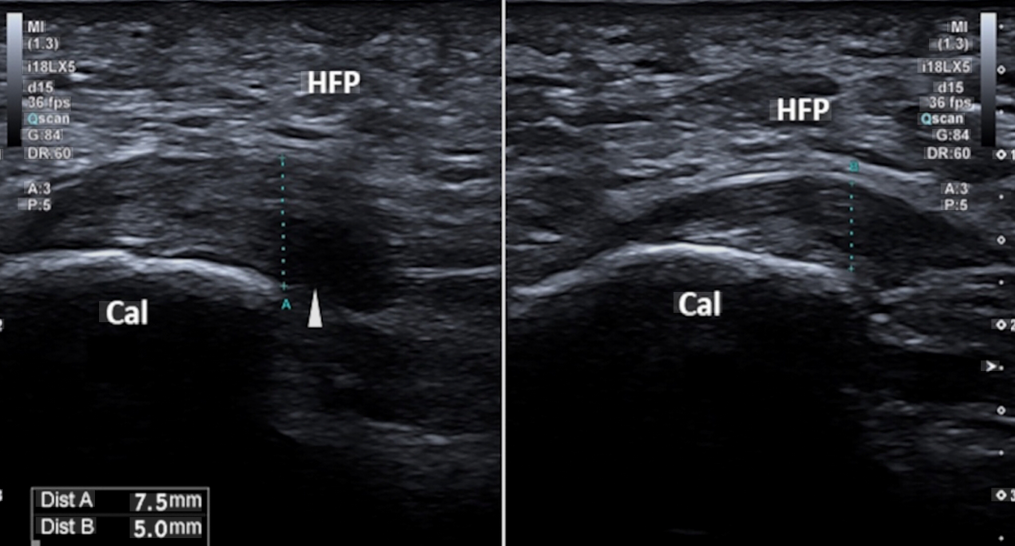

En una ecografía, es habitual observar una fascia plantar con un grosor superior a 4 mm, un hallazgo muy frecuente en pacientes con dolor plantar.

Pruebas de imagen

La ecografía es una prueba muy útil para valorar:

• El grosor de la fascia plantar

• Signos de inflamación

• Cambios degenerativos del tejido